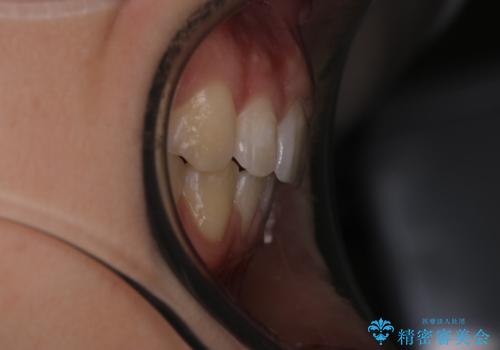

出っ歯の矯正 抜歯をしてしっかり引っ込めるワイヤー矯正

- 出っ歯を気にして来院されました。

しっかり前歯を下げるために抜歯を合計3本行いワイヤーにて矯正を行う計画としました。

見た目もよくなり、口も閉じるようになったと満足していただけました。

予定よりも早く終了することができたことにも喜んでいただけました。